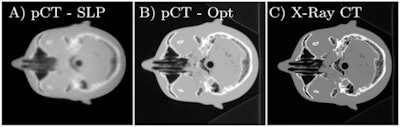

In computer simulations, Collins-Fekete and colleagues tested their statistical tool -- which they call a "maximum likelihood least squares estimator" -- on three different tissue phantoms. Adopting a widely used metric for the quantification of spatial resolution in imagery, known as MTF10%, the researchers found they could improve the resolution of a bare proton image with their tool by 65%. The resolution boost was the same as that delivered by existing methods, even though it required no prior radiographic imagery.